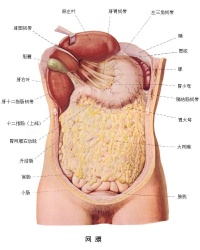

腹膜是指在存在高等脊椎动物腹腔中的一层黏膜,主要由间皮细胞构成,藉由结缔组织的支持所形成的一层膜状组织。腹膜包覆大部分腹腔内的器官,能分泌黏液润湿脏器的表面,减轻脏器间的摩擦。腹腔脏器的血液、淋巴和神经组织经由腹膜与外界相连。腹膜也具有吸收撞击保护内脏的效果。

腹膜(peritoneum)为全身面积最大、配布最复杂的浆膜,由皮及少量结缔组织构成,薄而光滑,呈半透明状。

衬于腹、盆腔壁内表面的腹膜称为壁腹膜(parietal peritoneum)或腹壁薄层;

覆盖腹、盆腔器表面的部分称为脏腹膜(visceral peritoneum)

脏腹膜与壁腹膜互相延续、移行,共同围成不规则的潜在性腔隙,称为腹膜腔(peritoneal cavity)。

腹膜腔是脏、壁两层腹膜之间相互移行围成的潜在性间隙。腹膜腔内有少量浆液,在脏器活动时可减少摩擦。

腹、盆腔的脏器依据被覆腹膜的多少可分为三类即:

(一)腹膜内位器官[编辑 | 编辑源代码]

此类器官几乎全部包被腹膜,活动度较大。主要的器官有:胃、十二指肠

上部、空肠、回肠、阑尾、横结肠、乙状结肠、脾、卵巢、输卵管等。

(二)腹膜间位器官[编辑 | 编辑源代码]

此类器官三面包被腹膜,活动度较小。主要的器官有:升结肠、降结肠、肝、膀胱、子宫等。

(三)腹膜外位器官[编辑 | 编辑源代码]

此类器官只有一面包被腹膜,几乎不能活动。主要的器官有:胰、肾、输尿管、肾上腺等。

(一)网膜[编辑 | 编辑源代码]

2.大网膜

2.原始腹膜腔和脏器的观察

打开腹膜腔后,可见贴附于腹内筋膜内面光滑的膜,即腹膜壁层;覆盖于脏器表面的光滑的浆膜为腹膜脏层。另外在器官与器官之间或器官与腹壁之间有腹膜形成物(韧带、网膜、系膜)相连。腹膜壁层与脏层、脏层与脏层之间的潜在腔隙即腹膜腔,正常情况下,仅有少量浆液存在,腹膜腔的形态随器官盈虚、运动等因素而变化。

在两侧肋弓围成的胸骨下角内,可见到肝膈面的一部分露出。肋下缘与右销赃骨中线相交处可见胆囊底。肝下缘与左肋弓之间可见到胃体及胃大弯的一部。自胃大弯向下垂有帘子状的大网膜,成人几乎复盖了胃下方全部的腹部脏器。小儿大网膜较短,仅能覆盖一部分脏器。

将大网翻起,可见蟠曲的小肠袢,小肠袢周围有大肠围绕,即居于右髂窝的盲肠和阑尾、右侧的升结肠、上方的横结肠、左侧的降结肠和左髂窝的乙状结肠等。